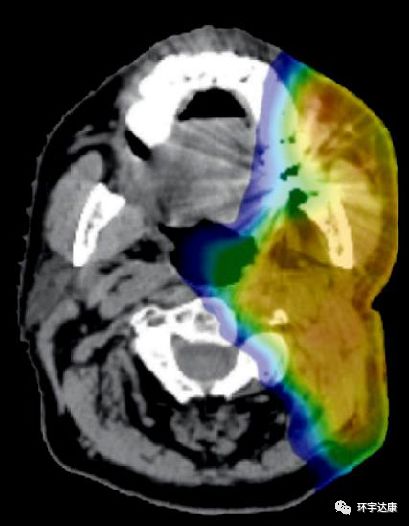

质子的辐射可以最大限度降低对正常组织的伤害,对目标肿瘤细胞造成最大的损害。以儿童髓母细胞瘤为例,我们可以看到普通放疗产生的大部分副作用,质子都完美的规避了。

普通放疗全部颅脑都受到照射

质子治疗